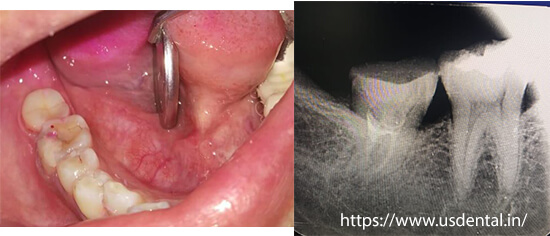

After root canal treatment, tooth preparation was done and onlay impressions were taken and sent to the lab to fabricate emax onlay.

A try in was done to check it is fitting and high points in occlusion.

Once the fit and occlusion was verified, final cementation was done with onlay luting cement.

The patient was happy with a smile, and she can eat more efficiently as well.